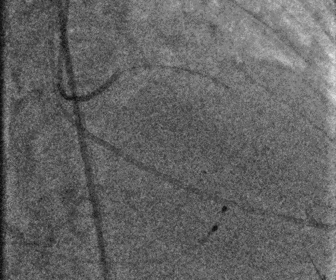

图片

左冠造影

左冠球扩

左冠支架植入

股动脉造影